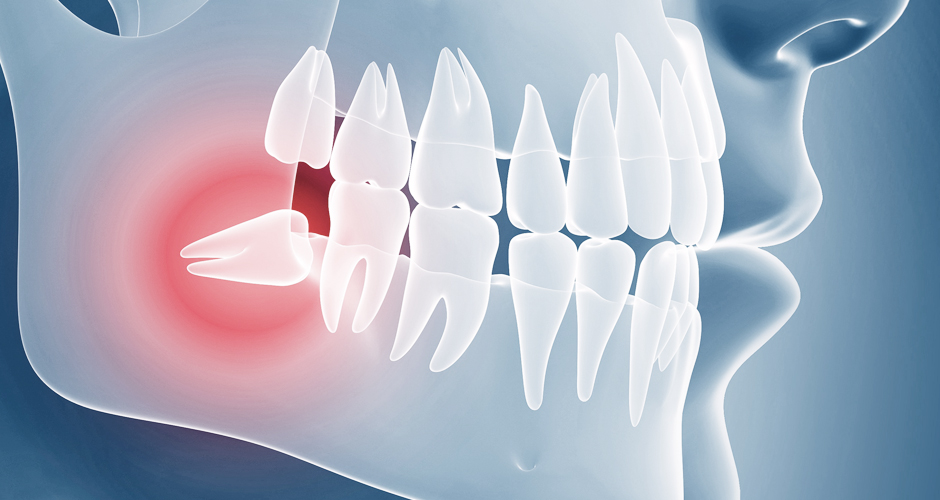

사선으로 자라 반은 잇몸안에 매복되어 있고

반은 잇몸 밖으로 나온 사랑니로

다른 치아에 손상을 입힐 수 있어 발치가 필요합니다.

안쪽에 있는 어금니의 뿌리가 흡수 될 수도 있고

다른 치아의 치열이 뒤틀릴 수 있어

발치가 필요합니다.